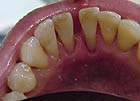

歯石

歯石とは

歯磨きで取れなかった磨き残し、つまり歯垢長い期間除去されずに石灰化して石のように歯に付着したものを指します。歯に歯石が長期間付着していると歯槽膿漏になり歯茎が腫れ、出血し、そして歯槽骨が溶け最後には歯がグラグラして抜けてしまいます。

一度歯石がつくと歯磨きではもう取れませんので、歯科医院で取ってもらわないといけません。

歯石除去しました